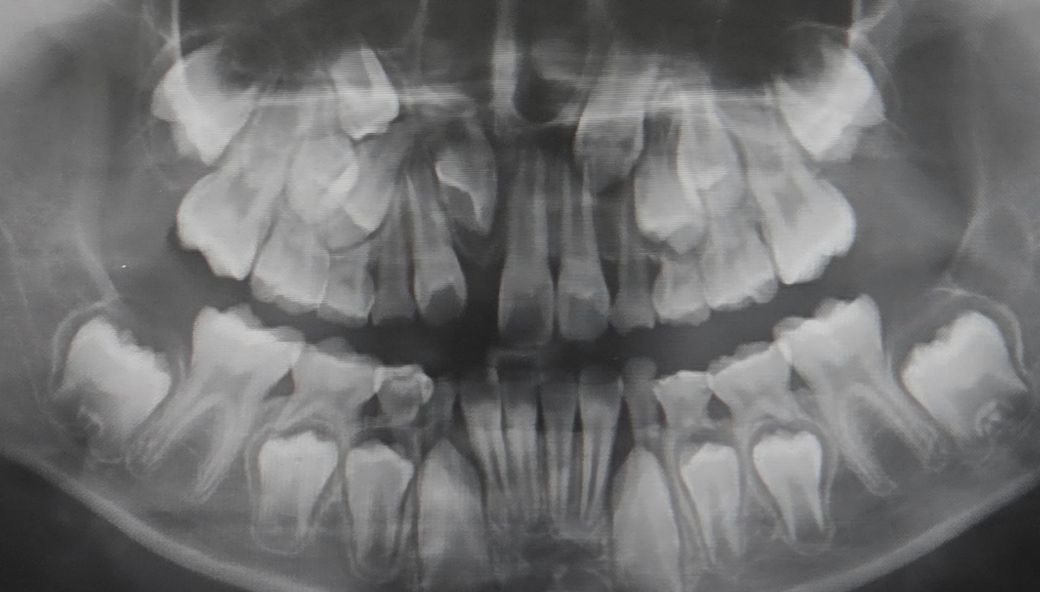

만8세아이 치아좀봐주세요. 앞니 한개가 안나오고있어요

문제는 앞니한개가 안나오고있어요

현재 11번 치아가 정상적으로 맹출되지 않고 있으며 오른쪽위의 송곳니 또한 맹출경로가 비정상적으로 보입니다.

성장기 교정으로 치아가 올라올수 있는 공간을 만들어줘야 할것으로 생각되며 오른쪽앞니의 경우에는 수술을 통한 견인이 필요할것으로 보입니다.

1. 공간이 부족하고 이미 잇몸뼈 안에서 치배상태에서부터 회전되어 있기 때문에 저 상태로는 나오기 어렵고, 교정치료로 적극 개입이 필요해보입니다.